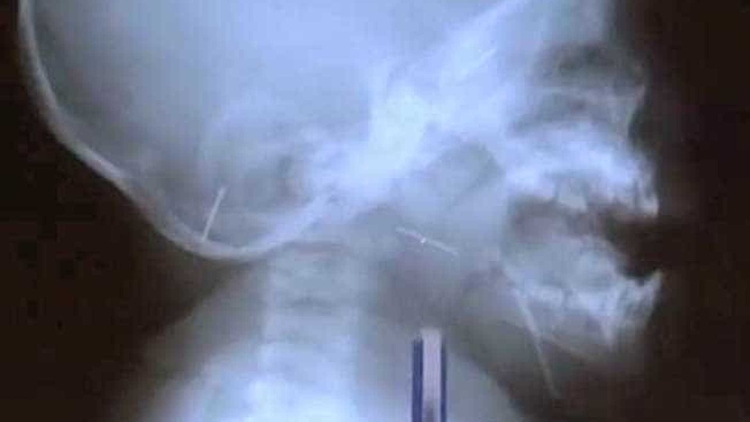

Por meio do raio-X, foram declaradas estruturas de metal presas no crânio, nariz, pernas, pescoço e peito da vítima. Os médicos afirmaram que o bebê não teria gerido as agulhas por acidente e seis já tinham sido retiradas do corpo do menino.

"Retiramos seis agulhas que já estavam enferrujadas dentro do bebê. Estamos nos preparando para realizarmos uma cirurgia para a remoção das agulhas alojadas no crânio e no estômago dele. Será um procedimento mais trabalhoso e que demanda uma cautela maior, e, por isso, não realizamos junto aos outros processos”, disse o cirurgião Shukhrat Choriev.